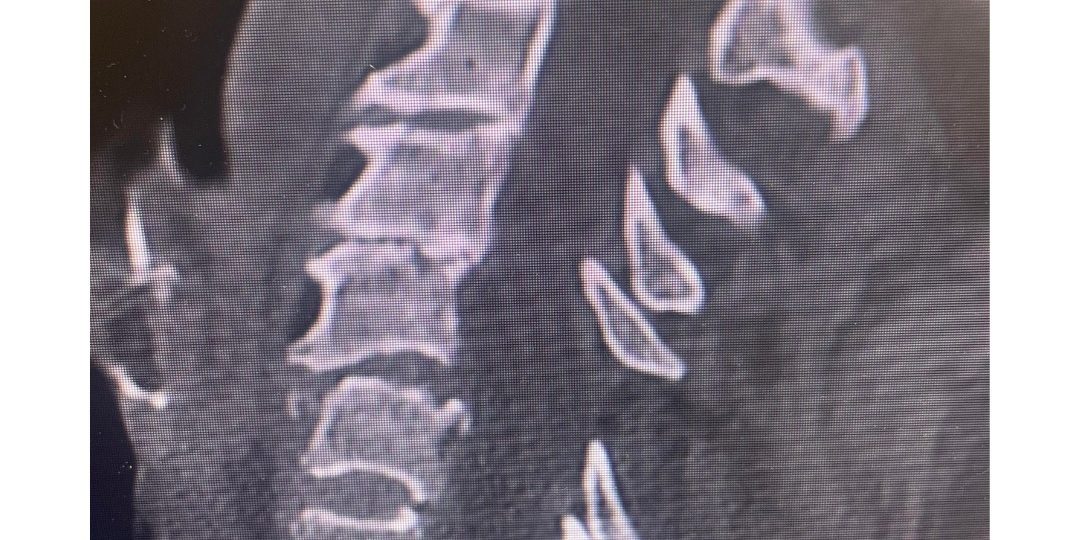

The first 2 pictures are a CT scan and then an MRI of the C5-6 fracture with spinal cord compression. The next is X-ray taken during surgery. The last is X-ray at 2 months postoperative. At 2 months after surgery, the patient is living at home again. She is as strong as ever!”